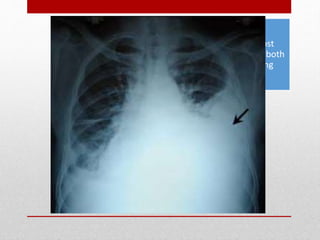

CHEST

• Blunt trauma to the chest may involve the:

• chest wall, thoracic spine, heart, lungs, thoracic aorta

and great vessels, and rarely the esophagus.

• Occult Thoracic Vascular Injury

• Penetrating Thoracic Trauma

Hemothorax and

Pneumothorax - most

common injuries from both

blunt and penetrating

thoracic trauma